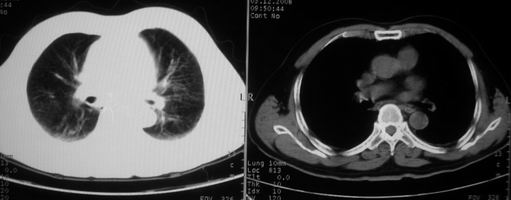

抗炎治疗一周热退,提示为炎症,现片示病灶范围增大,边缘清楚,建议继续治疗,不除外肺脓肿

炎症性病变;左侧胸腔积液。

ct左肺下叶大片状高密度影,病变密度不均,界限不清,左侧胸腔积液,治疗后复查临床症状好转而影像学表现病变有发展,还是首先考虑感染性病变,复查时间短附合感染性病变的病理改变。